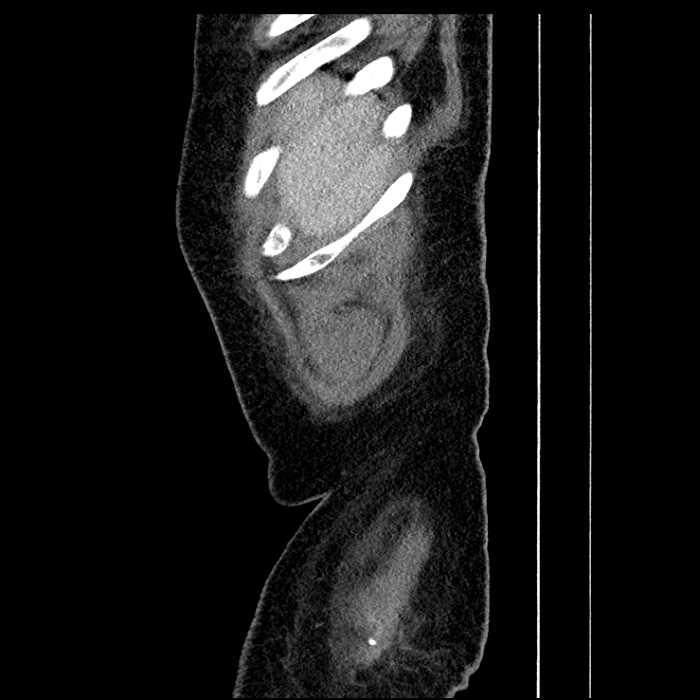

Age: 63

Sex: Male

Indication: Abdominal pain

• Large fluid density structure in hepatic segments 7 and 8 measuring 10 x 7 x 7 cm with internal septation and circumferential ill-defined low density compatible with edema

• Peripherally enhancing subcapsular collections along the anterior margin of the left hepatic lobe measuring 3 x 1 cm and 2 x 1 cm

• Hepatic abscess

Acute sigmoid diverticulitis complicated by a small contained perforation and a large abscess in the right hepatic lobe. Additional small subcapsular abscesses along the anterior margin of the left hepatic lobe.

• The classic CT imaging appearance is a double target sign with internal low density surrounded by an internal enhancing rim (capsule) and a low density external rim (edema)

Hepatic abscess showing the double target sign with low density internally surrounded by a thin inner enhancing rim (red arrow) and ill-defined outer low density rim (yellow arrow). Blue arrow indicates an internal septation. Red arrows: additional smaller subcapsular abscesses. Red arrow: focal contained perforation associated with diverticulitis.